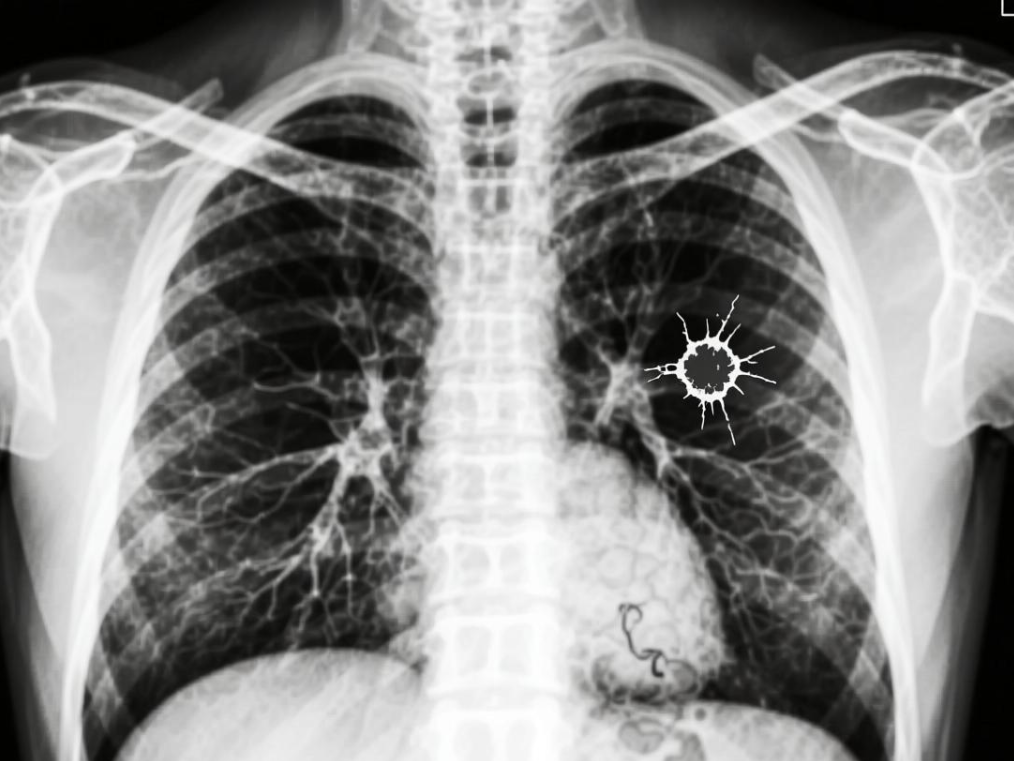

肺腺癌:起源于肺部支气管黏膜的腺上皮细胞,癌细胞能分泌黏液,多发生在肺部的周围区域(靠近肺的边缘),故而也称之为“周围型肺癌”。

形象点说,肺鳞癌更像长在肺部“主干道”附近的肿瘤,而肺腺癌更像长在肺部“分支小路”末端的肿瘤位置不同,后续的症状和检查发现难度也会不一样。